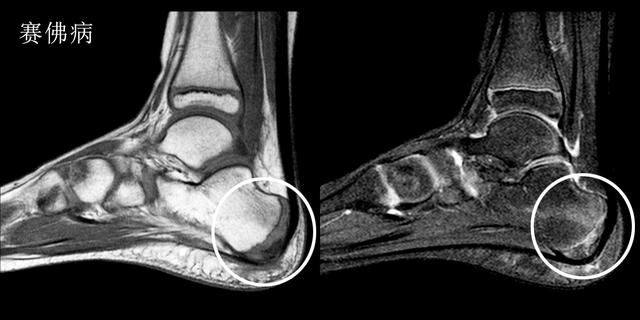

赛佛病---孩子也会得的跟痛症

足部是第一个成长为全尺寸的身体部位之一。这通常发生在青春期早期。在此期间骨骼通常比肌肉和肌腱生长得更快。结果肌肉和肌腱变得紧绷,使鞋跟区域变得不那么柔软。在承重活动期间,会伤到脚跟诱发疼痛导致塞弗病(Sever's Disease)。

赛佛病主要的症状是在运动时,尤其是跑跳时出现明显的足跟痛。

在生长突增期间,您的孩子在青春期早期受伤的风险最大。

Sever病在8至10岁的身体活跃女孩中最常见。最常见的是10岁至12岁的身体活跃男孩。足球运动员和体操运动员经常得到塞弗病。任何跑步或跳跃活动的儿童也可能面临更大的风险。Sever's疾病很少发生在年龄较大的青少年身上,因为足跟的背部通常在15岁时完成。

这种疾病诊断主要还是依靠核磁检查,在核磁图像中我们可以看到明显的跟骨周边的无菌性严重表现,从而判断孩子是否得了赛佛病。

这种疾病的治疗以保守治疗为主,冰敷、休息以及外用药物可以得到很好地治疗效果。